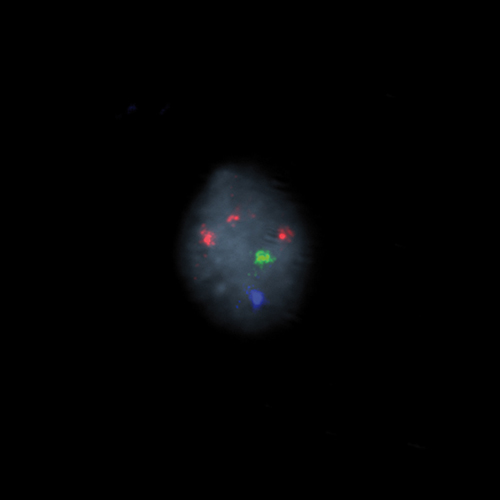

Hybridization of the RCAN1 (21q22), SE X, SE Y probe to a male metaphase spread showing normal pattern (2R1G1B)

IVD RCAN1/SE X/SE Y

KBI-40008

RCAN1 (21q22), SE X, SE Y